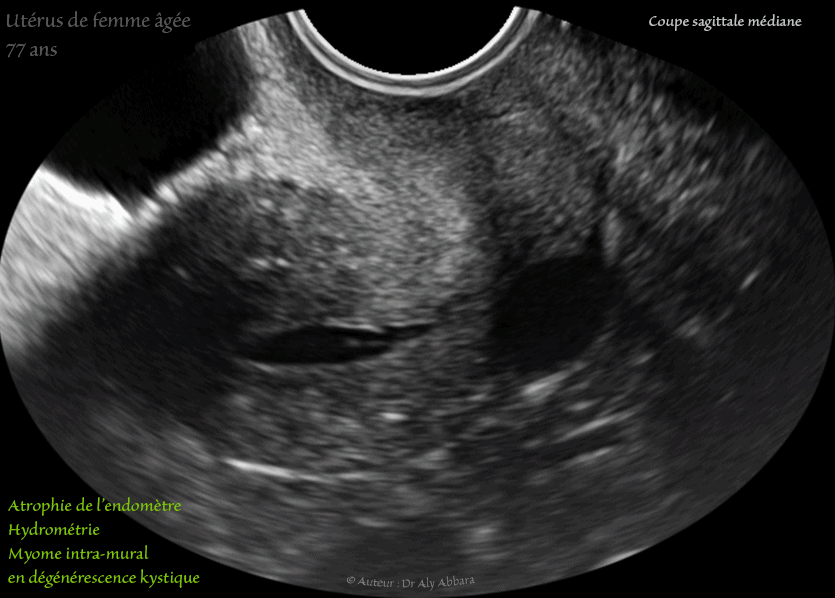

Utérus d'une femme âgée de 77 ans - hydrométrie - atrophie de l'endomètre - myome en dégénérescence kystique

Images échographiques animées montrant l'utérus d'une femme âgée de de 77 ans, avec plusieurs éléments anatomiques liés au vieillissement (sénilité)

I- Hydrométrie :

Il s'agit d'une rétention des sécrétions endométriales dans la cavité utérine liée à la sténose, voire l'obstruction totale du canal cervical.

II- Atrophie de l'endomètre :

Elle est la conséquence de l'effondrement du taux des estrogènes par l'inactivité de la fonction hormonale ovarienne.

III- Myome utérin intramural type 4 (de classification FIGO) en dégénérescence kystique